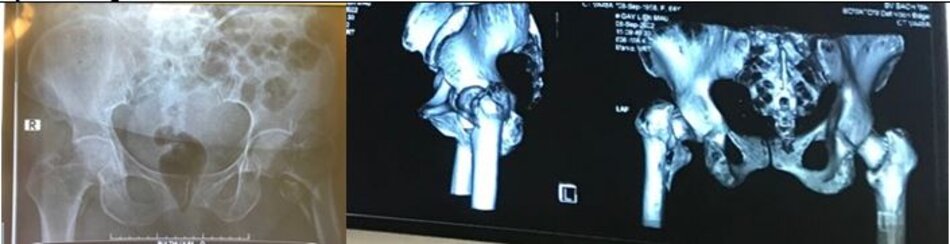

Phẫu thuật đường sau (Vỡ ổ cối)

X quang trước mổ

X quang sau mổ

Hình ảnh đường mổ